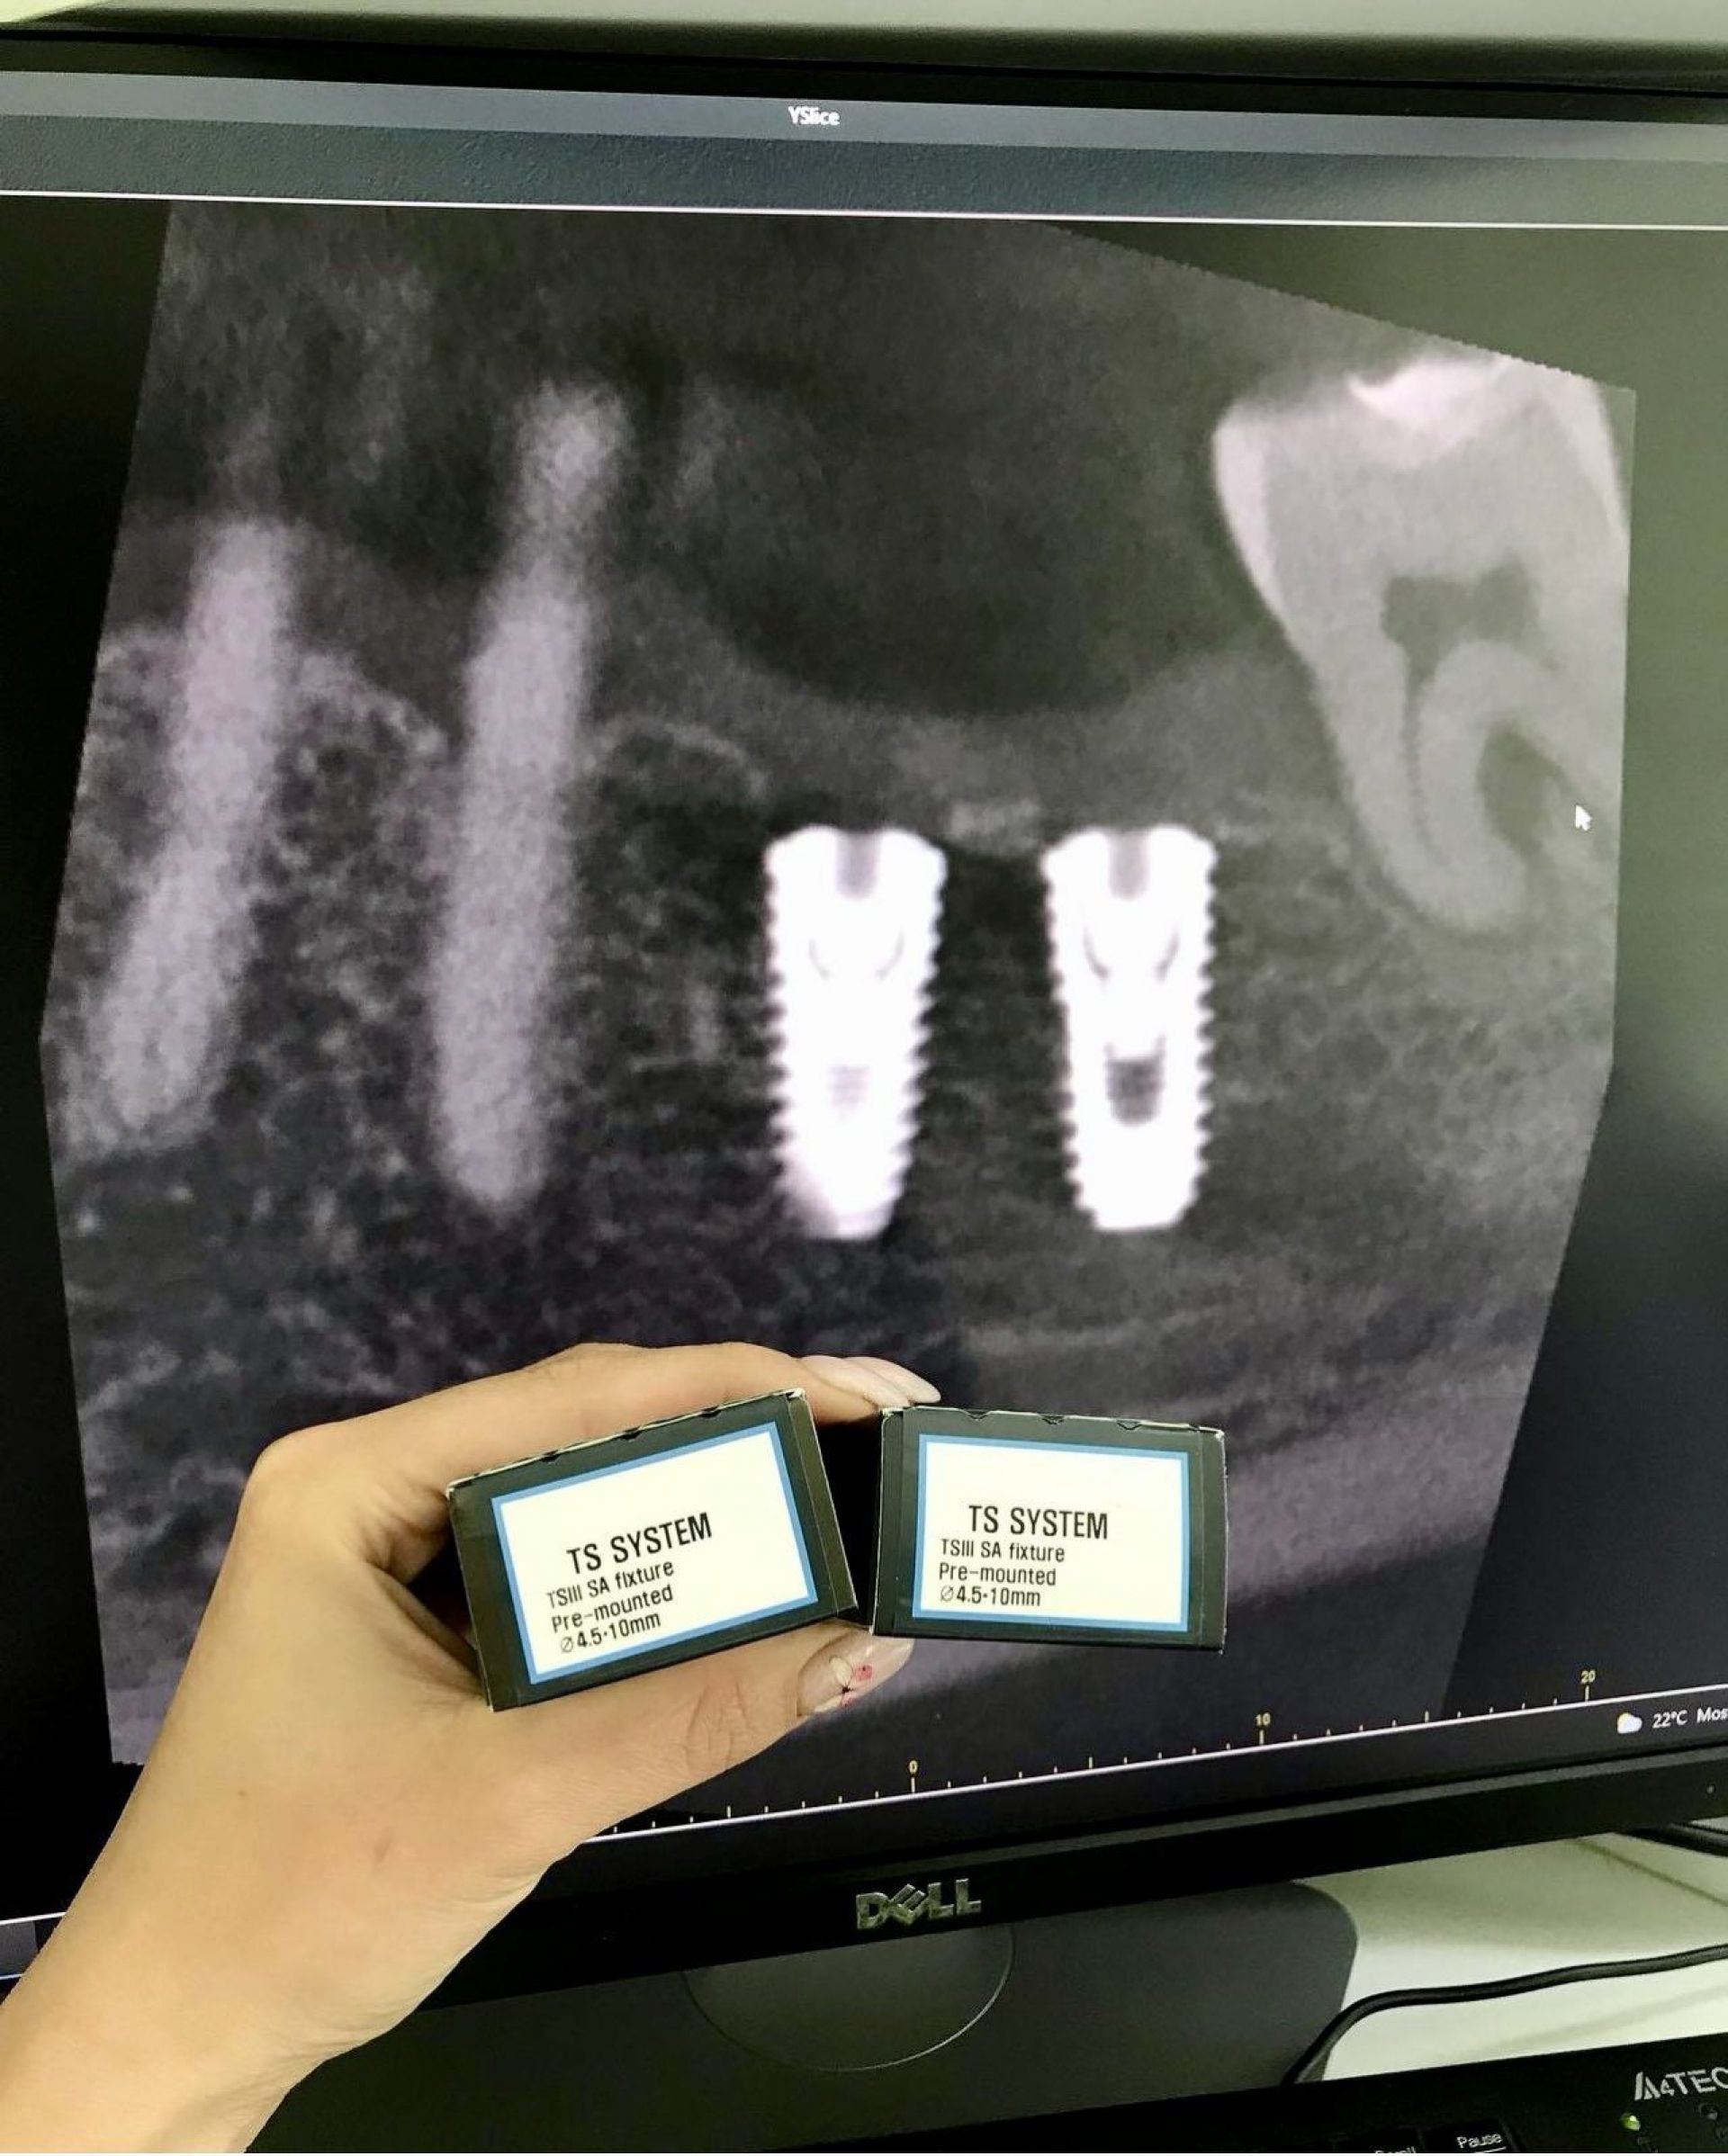

В AsProDent працюють лише з всесвітньо відомими та якісними системами імплантів.

Ще один важливий фактор, який вигідно відрізняє клініку INNOVA від конкурентів – власний комп'ютерний томограф. Таким чином, можливо провести комплексну діагностику перед плануванням операції. Дані КТ зубів дозволяють не лише оцінити стан кістки пацієнта, а також дозволяють виготовити спеціальні хірургічні шаблони для майбутньої операції та оцінити становище імплантату відразу після операції.

З безлічі сучасних систем в клініці використовують імплантати від перевірених надійних виробників Osstem; Neodent; Straumann.

У своїй роботі в клініці використовують імпланти тільки перевірених і кращих світових виробників (Південна Корея, Швейцарія тощо).

В МНВЦ "Плоскирів" найголовнішим критерієм є якіст послуг і для цього у них є все: досвідчені лікарі, кращі матеріали, найсучасніші цифрові 3D-технології, обладнання та власна зубопротезна лабораторія.